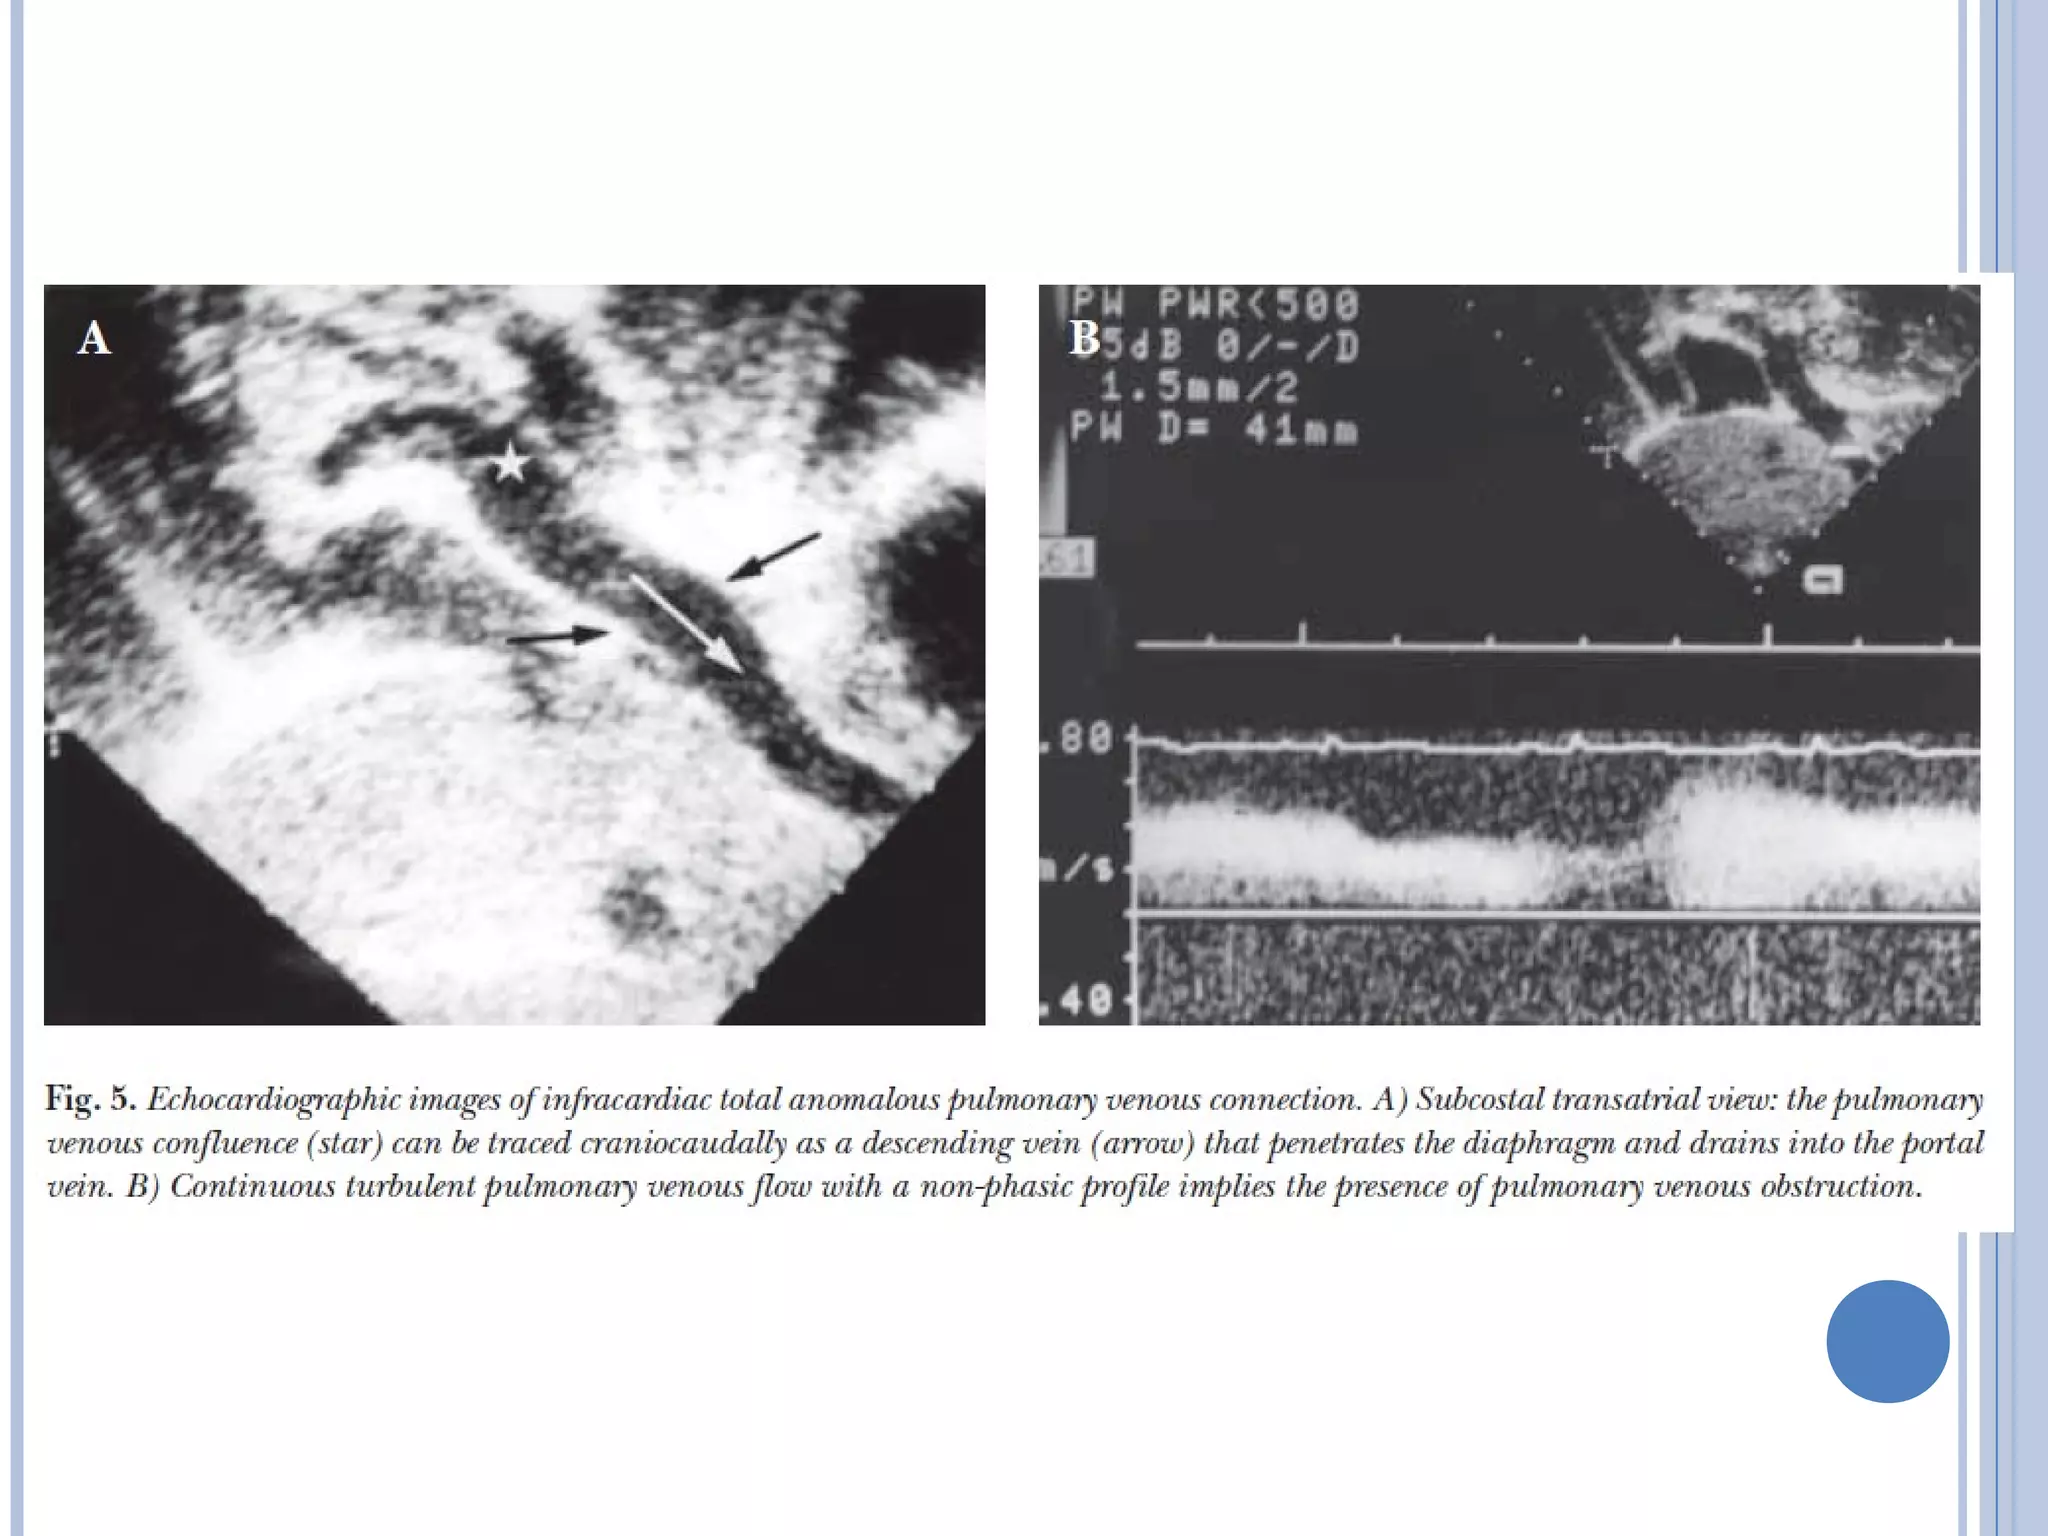

 Descending anomalous vein is characterized

by the venous flow pattern and direction of

flow is away from the heart towards abdomen.

 An increased flow velocity, turbulent flow pattern

and loss of phasic variations characterize

obstructed pulmonary venous flow. (normal venous

flow is low velocity, phasic laminar pattern with

brief flow reversal during atrial systole)